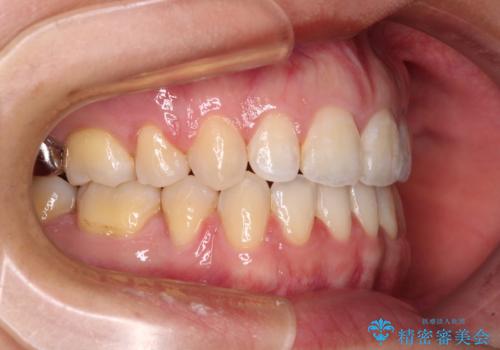

- 唇の閉じにくさを気にして来院された患者様です。

上下左右第一小臼歯4本を抜歯し、ワイヤー装置にて口元を引っ込めるよう矯正治療を行うこととしました。

骨格的に下顎がやや前方にあるため、横顔のシルエットが著しく変化することはありませんでしたが、口元はスッキリと引っ込み、唇が閉じやすくなりました。